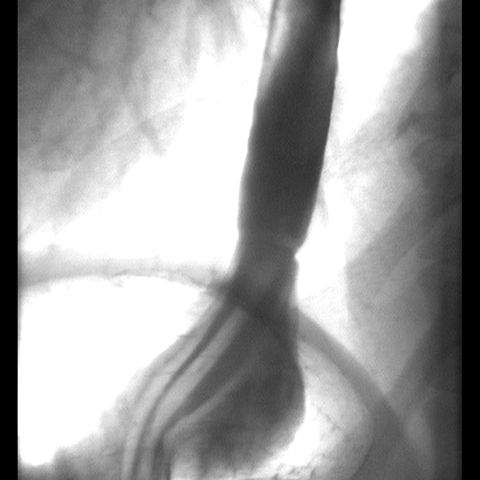

Hiatal Hernia, Barium Study [2 of 2]